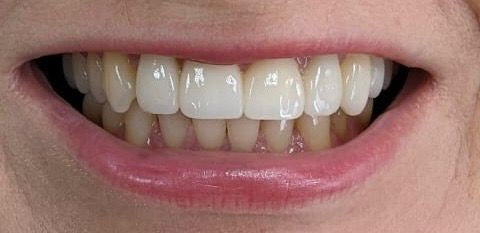

Установка коронки из диоксида циркония

Диоксидциркониевые конструкции цифрового моделирования на зубы верхней челюсти.

Состояние после снятия старых коронок и фото в день фиксации.